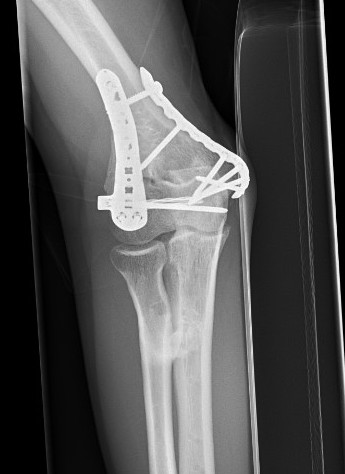

Xray

Radio-ulna synostosis

CT

Define anatomical location of the HO prior to surgical excision